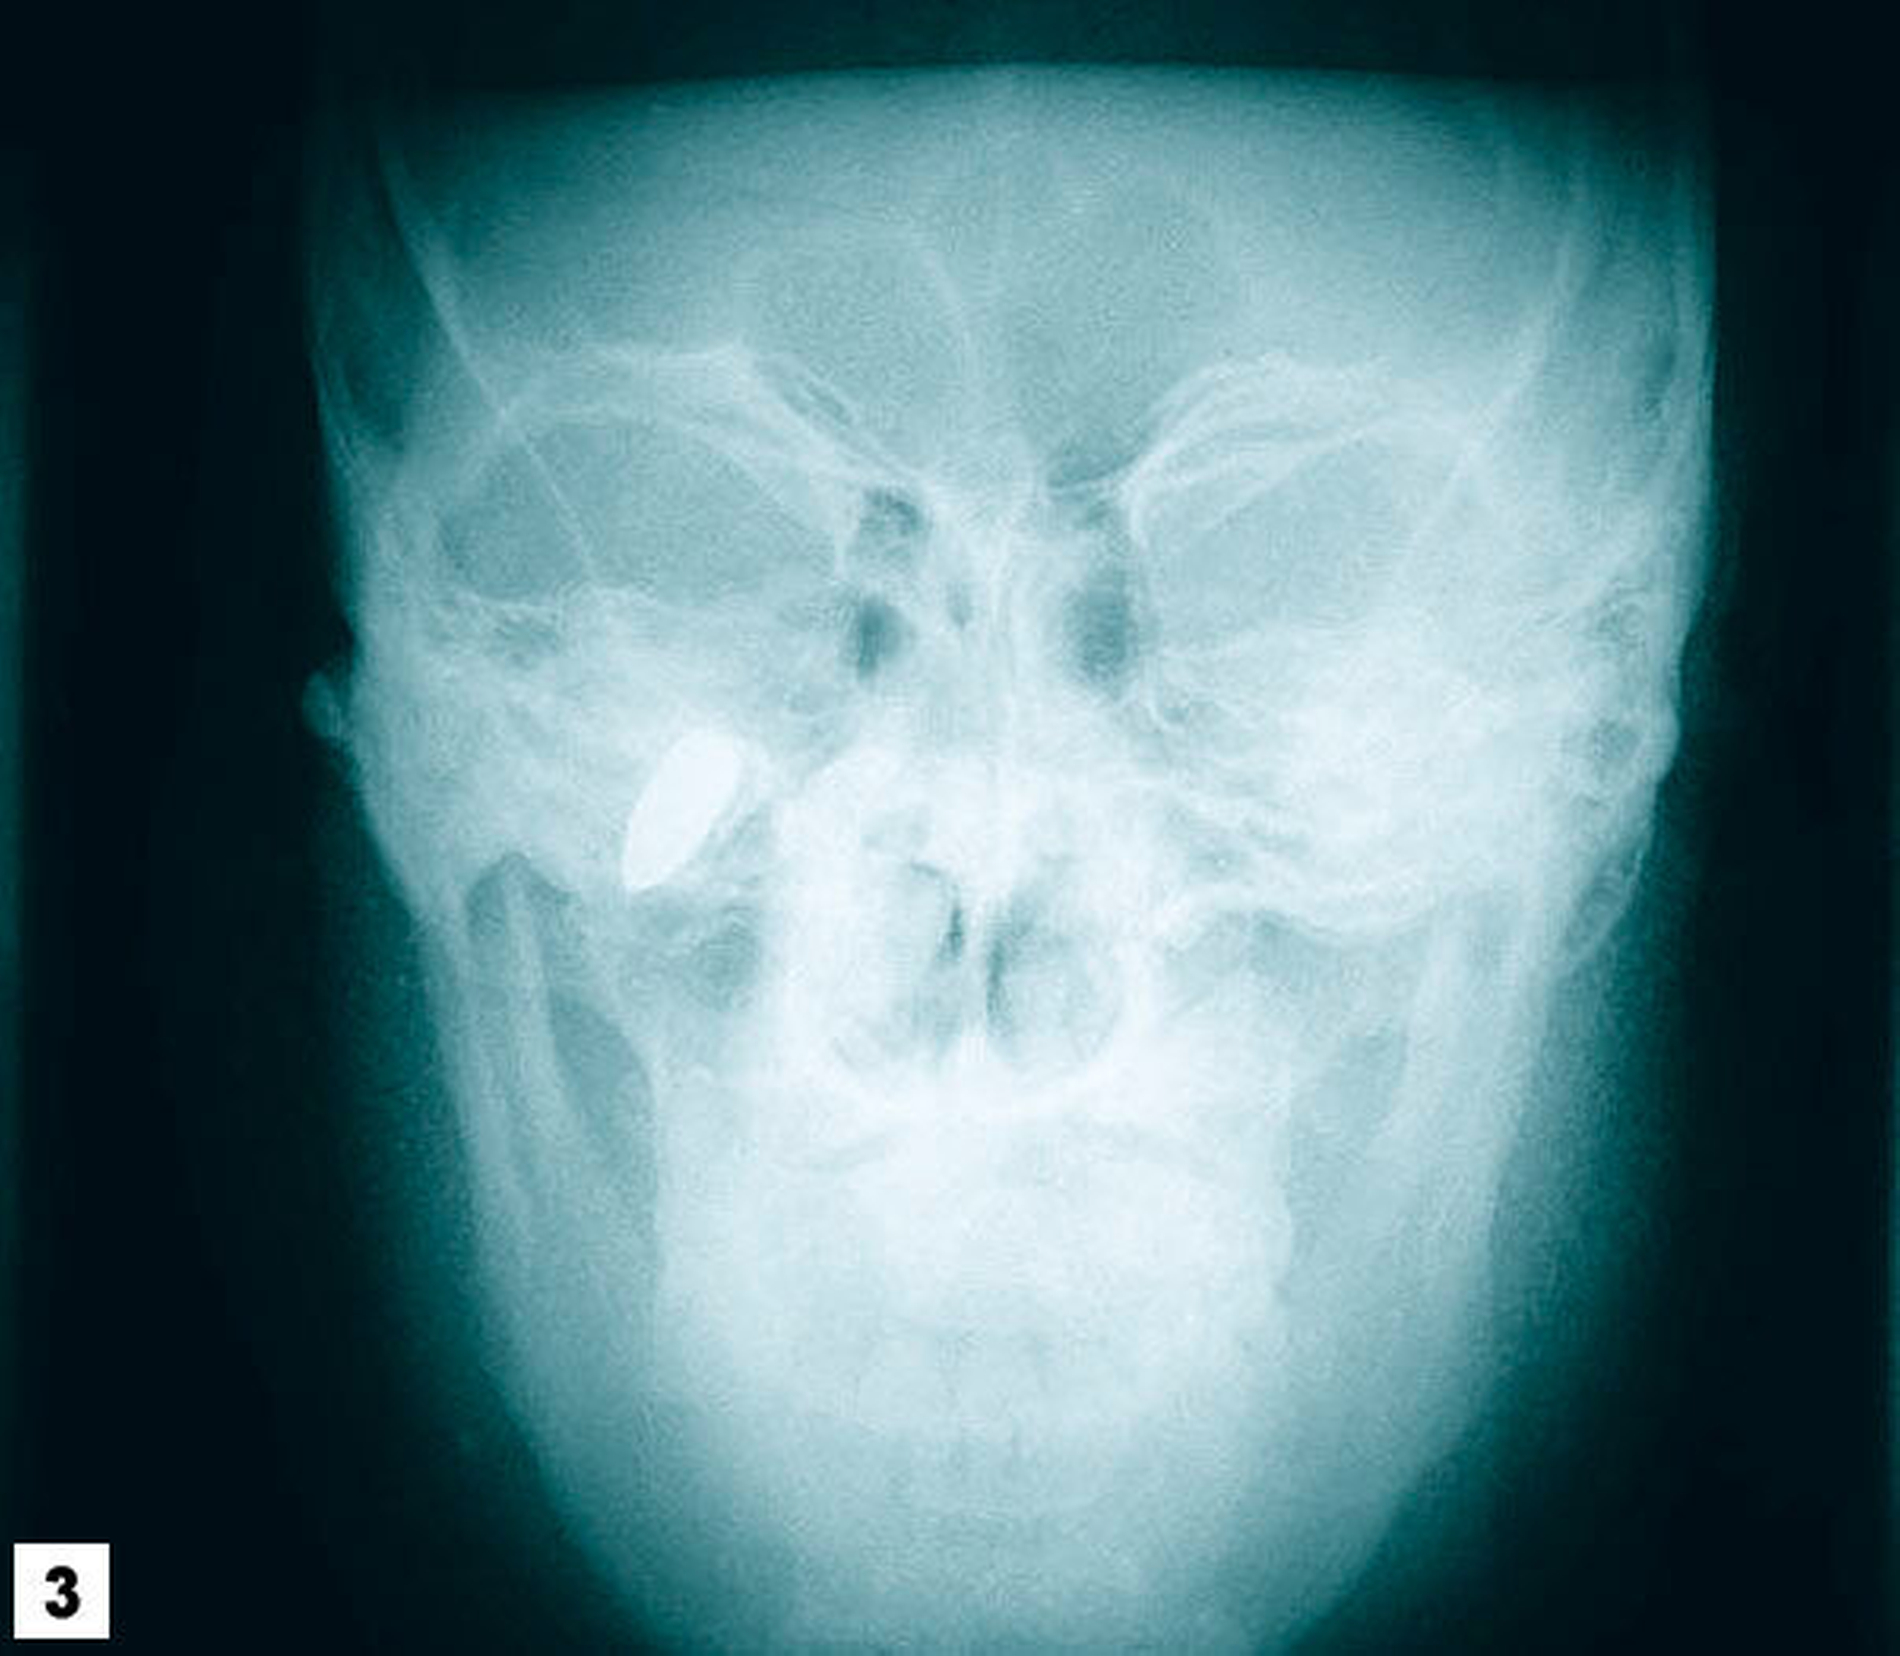

Der Patient ist afghanischer Herkunft, war (soweit bekannt) gesund und in gutem Allgemein- und Ernährungszustand. Klinisch zeigten sich eine Dichromatie und eine leichte Lidspaltenöffnungsdifferenz (Abbildung 1). Die intraorale Inspektion war weitgehend unauffällig. Die von der Chirurgin mitgelieferten Nativröntgenbilder ließen eine apikale Osteolyse in der Region des Zahnes 37 vermuten, zudem zeigte sich ein metalldichter Fremdkörper mit Projektion auf die Kieferhöhle rechts (Abbildungen 2 und 3).